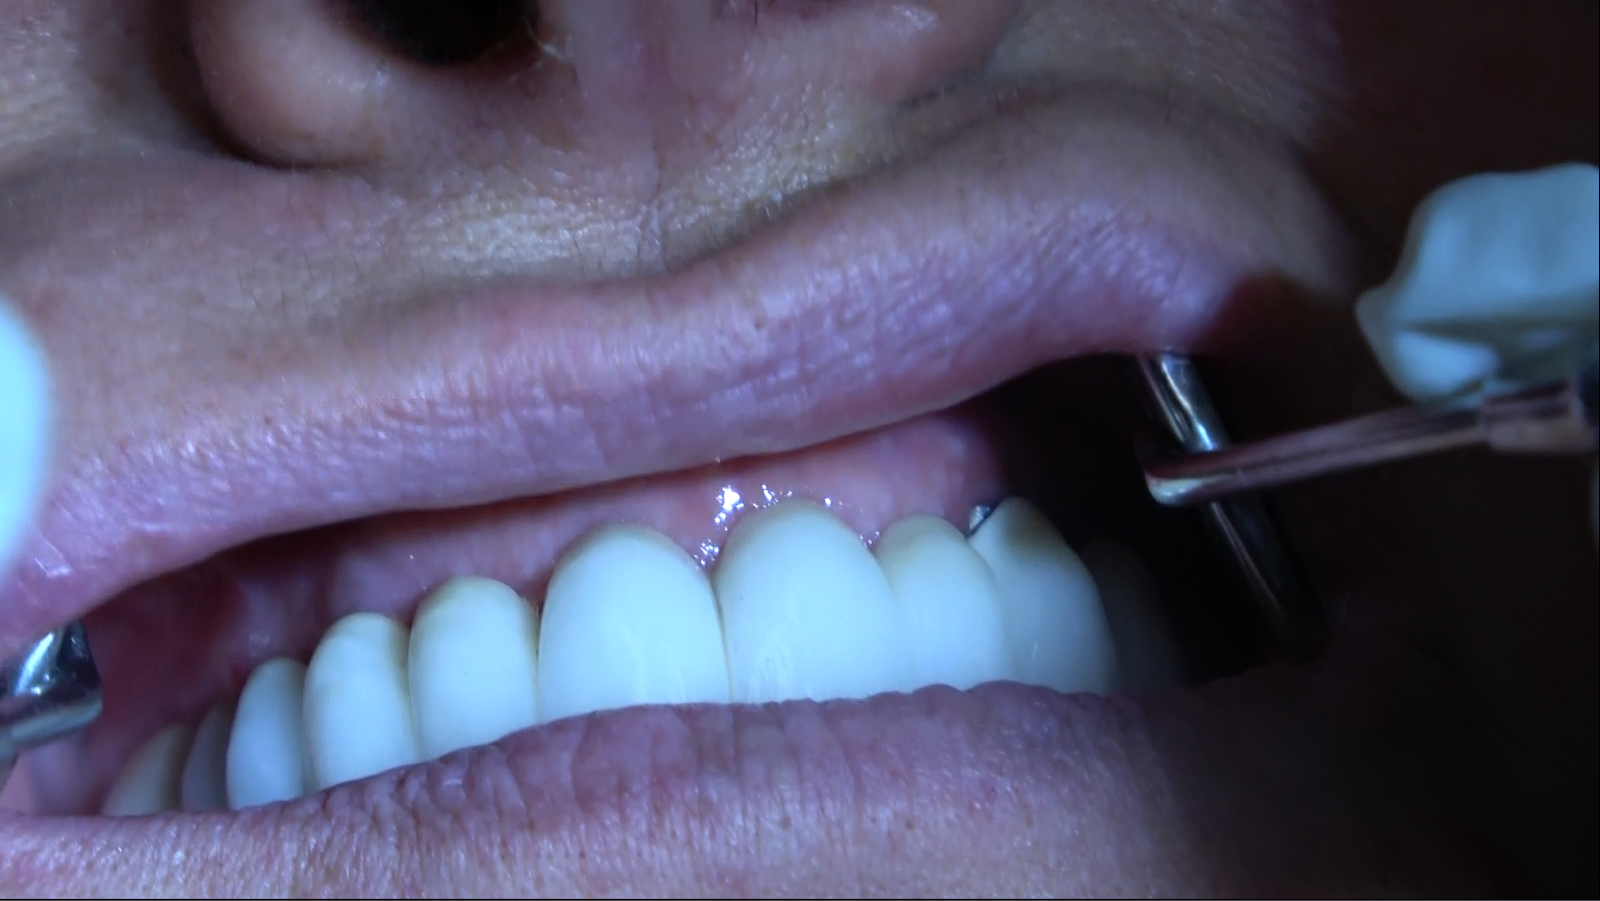

• Galleria Fotografica:

• La nostra galleria fotografica presenta una collezione di sorrisi trasformati grazie alle nostre protesi circolari. Scopri i risultati straordinari ottenuti per i nostri pazienti.